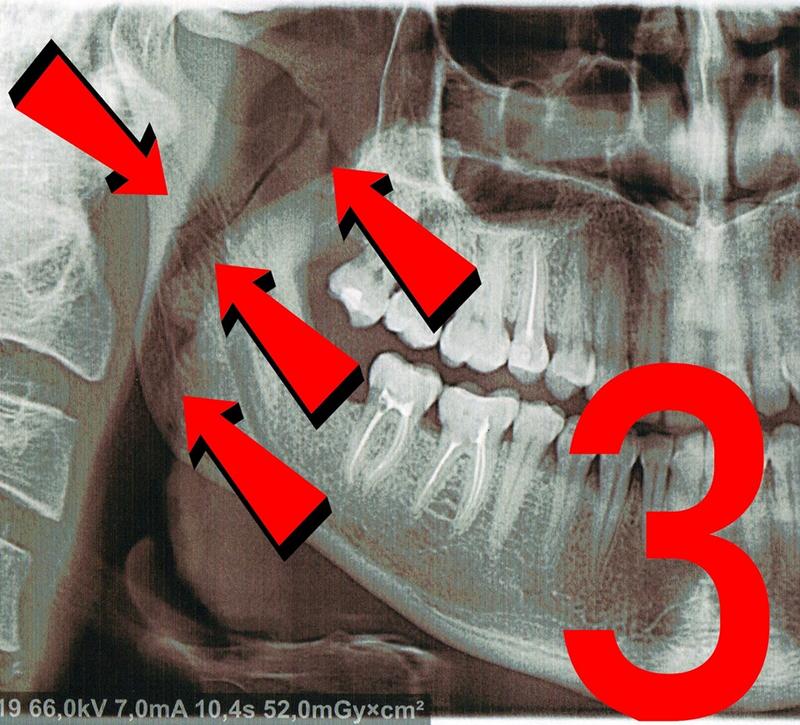

После этого мужчина достал телефон и начал фотографировать автохама. Водитель вышел из машины и направился в сторону Евгения, а потом ударил его в правую часть лица. В результате чего, он получил перелом нижней челюсти справа в области суставного отростка.